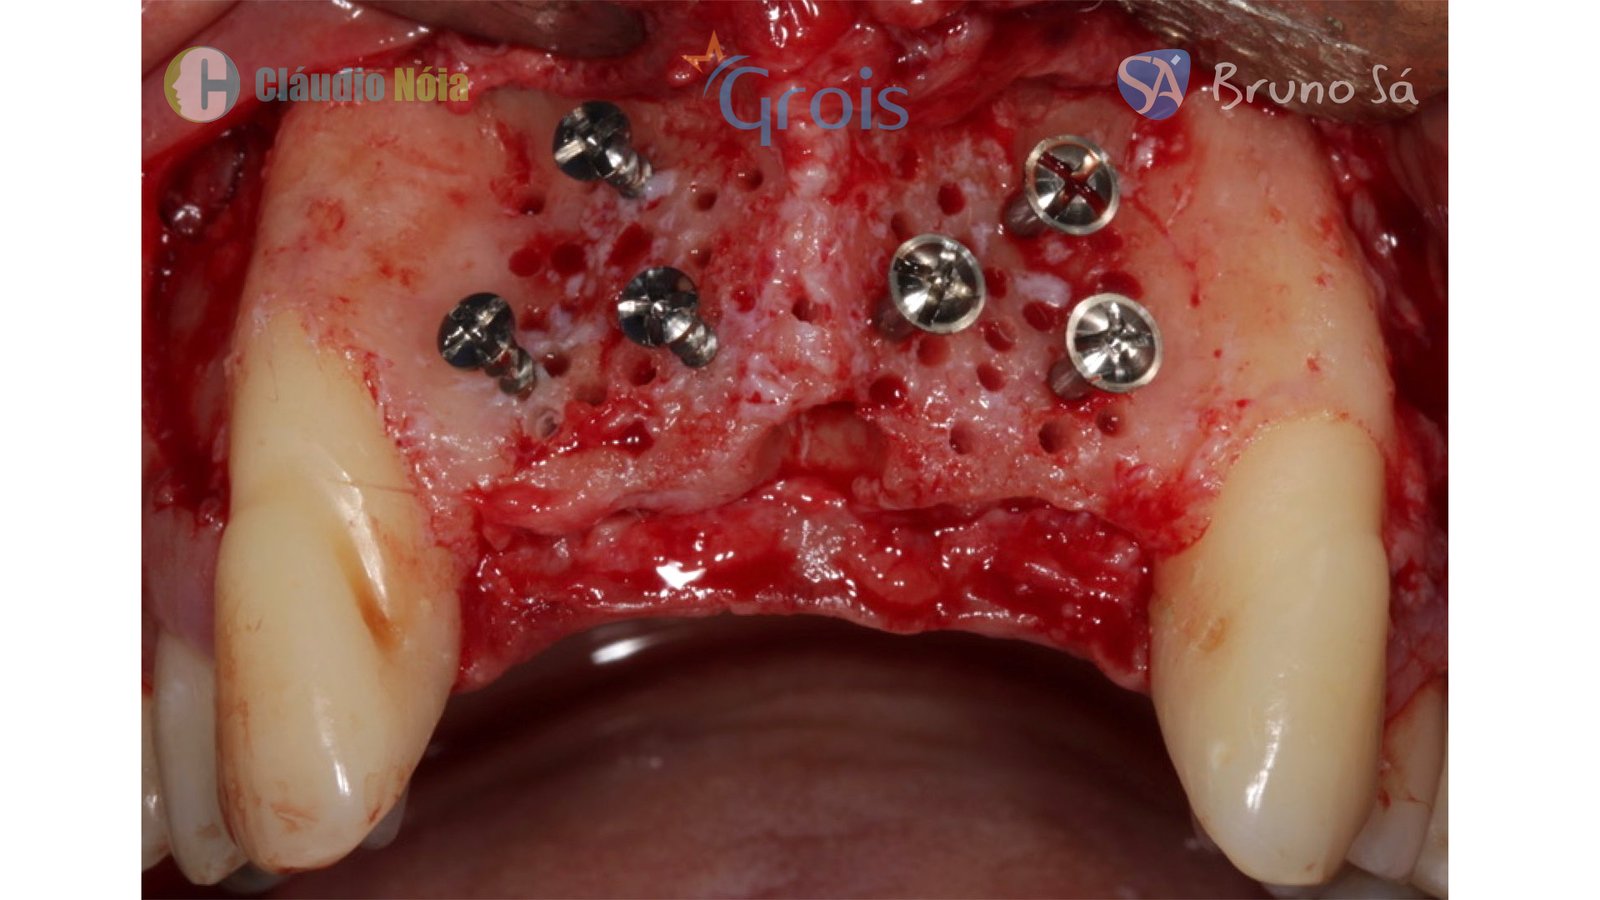

Paciente apresentou-se a Área de CBMF da Instituição com a pré-maxila edêntula (Figuras 1, 2 e 3) e foi submetido a técnica Screw Tent Pole utilizando os parafusos da linha Orth – Implacil de Bortolli (Figura 3). Do lado direito da pré-maxila foram instalados 3 parafusos que apresentavam roscas em toda superfície, enquanto que do lado esquerdo foram instalados 3 parafusos que não apresentam roscas no terço cervical (Figuras 4, 5, 6, 7 e 8). Biomaterial associado com PRF (Stick Bone) foi adequadamente acomodado na região e recoberto por membranas de PRF (Figuras 9, 10 e 11). Uma sutura livre de tensão foi realizada para finalizar o procedimento cirúrgico (Figuras 12 e 13).